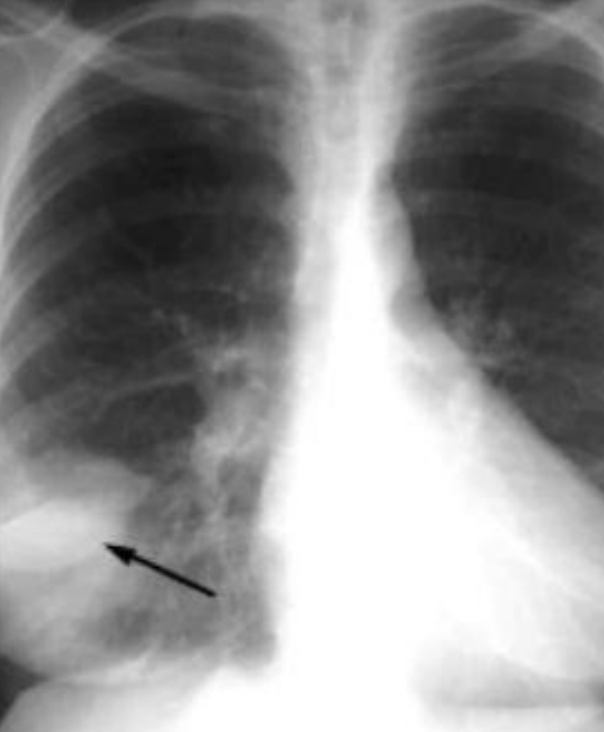

Joroba de Hampton:

Osificación pleural en domo secundaria a hemorragia e infarto

Joroba de Hampton